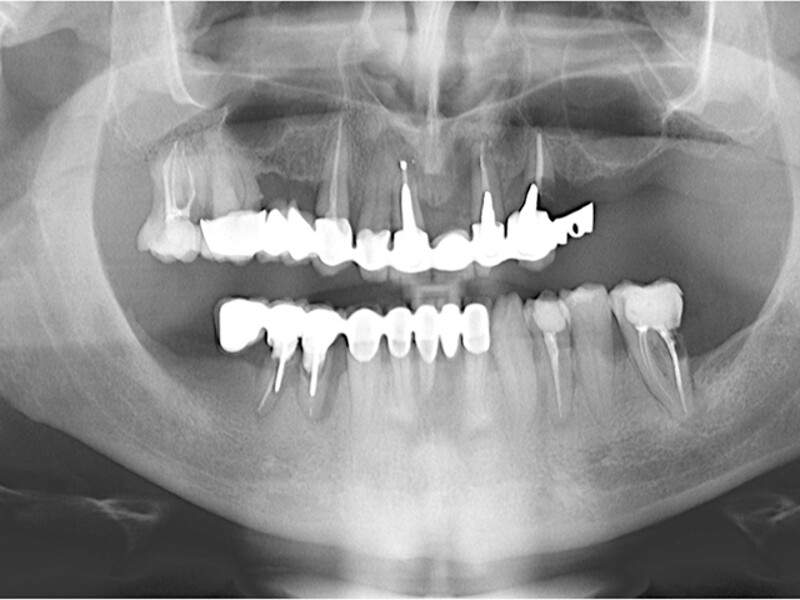

MAGICAL All on FOUR